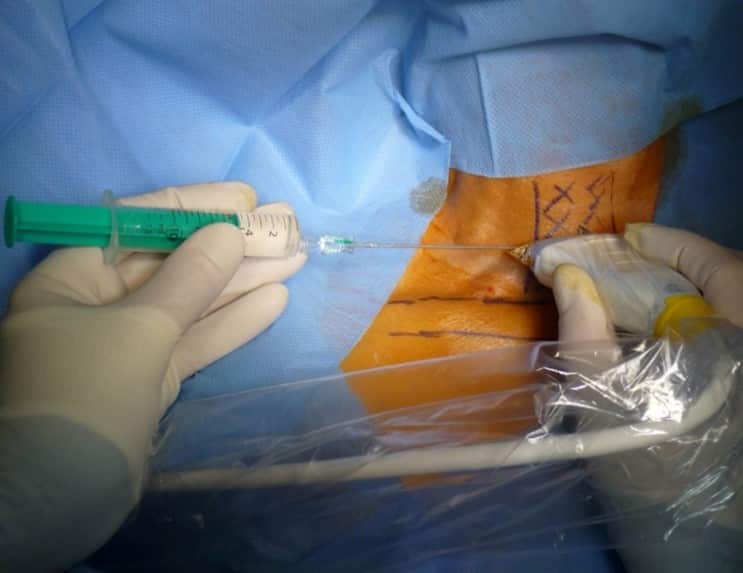

3. Acceso por la vena subclavia en adultos

La vía subclavia en comparación la vía yugular es más funcional y estética evitando muchas de las complicaciones relacionadas con la punción a ciegas.

Además, no es necesario tunelizar, es un abordaje más cómodo et rápido.

Hoy en día, nuestra vía de abordaje de elección era la vena subclavia en el surco deltopectoral, lo cual permite una gran discreción para los pacientes (respeto del escote). Colocamos el 99% de nuestros puertos con este abordaje.

Se han realizado alrededor de 10.000 procedimientos en nuestro instituto desde 2007, con esta técnica y con esta técnica no hubo casos de neumotórax, punción arterial o síndrome de Pinch off.

En este caso, se crea el bolsillo de un tamaño ajustado al tamaño de la cámara ya que no se sutura a los tejidos subcutáneos. Eso permite que no se de la vuelta y evita las grandes dificultades que existen a la hora de la retirada cuando se sutura.

Se punciona la vena en el fondo del bolsillo: de esta manera el catéter tiene un recorrido más fisiológico y evitamos los posibles curvas o acodamientos que pueden crearse cuando la vena se punciona desde otro lugar.